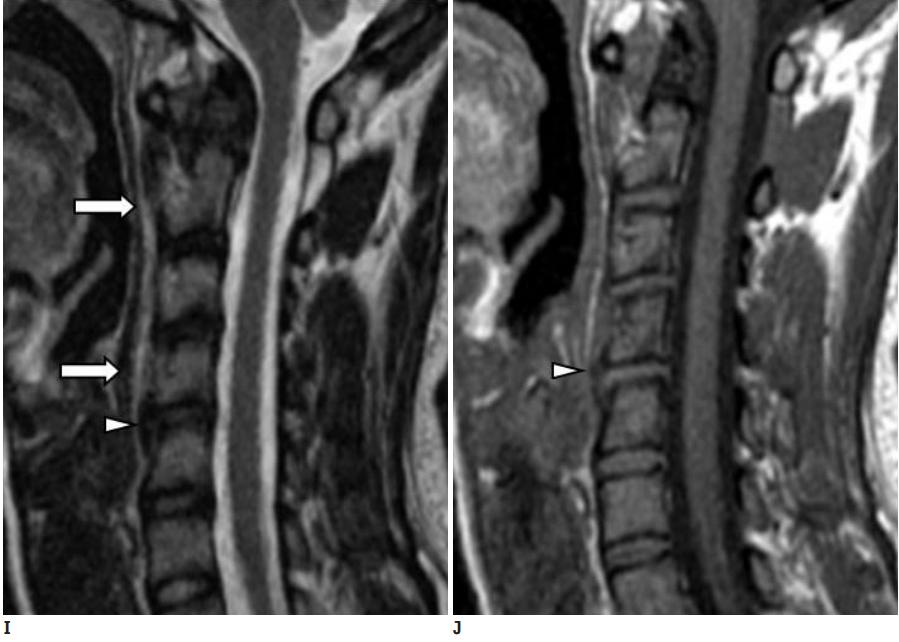

C1-2前侧低信号(无线箭头)和C1-5椎前水肿(长箭头)

(PMID: 19567634)

上述病人,I和J: 入院4天后复查颈椎MRI示椎前积液明显减少; K,随访2个月复查CT示C4-5前钙化灶减小。(PMID: 21852912)